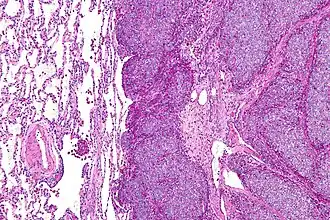

Гистологическая картина

Классическая гистологическая картина саркомы Юинга представлена бесструктурными агрегатами мелких опухолевых клеток, разделенных фиброзными прослойками. Клетки имеют правильную форму, содержат округлые или овальные ядра, характеризуются высоким ядерно-цитоплазматическим отношением. Заключенная в клеточных ядрах дисперсия хроматина придает им характерный «зеркальный» вид. Митотическая активность в клетках саркомы Юинга, как правило, низкая. Зачастую при патоморфологическом исследовании определяется выраженный некроз опухолевой ткани, с преимущественной локализацией жизнеспособных клеток вокруг сосудов. Особенности морфологии саркомы Юинга затрудняют проведение дифференциальной диагностики с другими мелкоклеточными злокачественными опухолями у детей (нейробластомой, рабдомиосаркомой, неходжкинской лимфомой, синовиальная саркома, лейомиосаркома и др.). Поэтому проведение биопсии недостаточно для постановки диагноза саркомы Юинга [9]